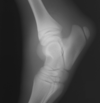

What is shown in these images?

tarsal DJD

-fuzzy, ill-defined joint spaces

-bone production

-abnormal joint spaces with bone production

What is seen in this DMPLO?

-abnormal joint space and bone production